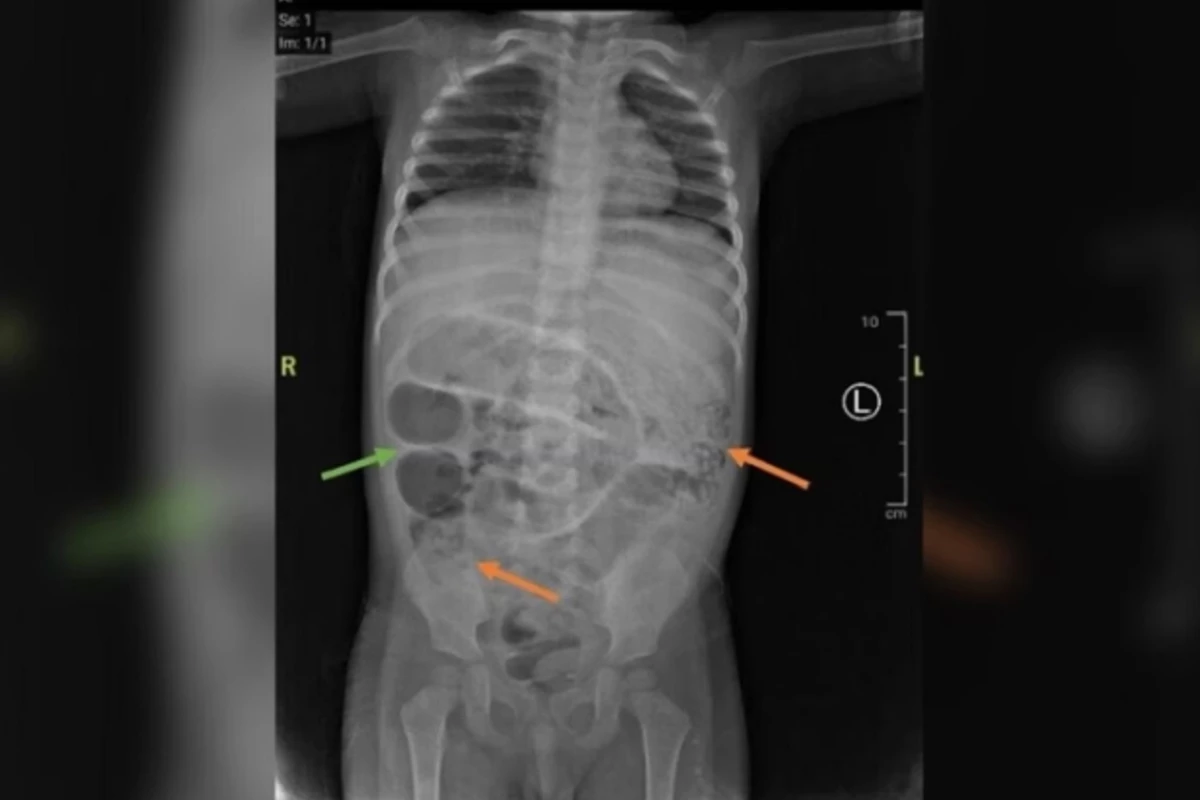

Depois das crises de vômito, a equipe médica realizou exames de imagem. A tomografia computadorizada detectou regiões opacas no intestino, compatíveis com obstrução. A situação se intensificou devido à anemia e à leucocitose, que é o crescimento dos glóbulos brancos no sangue e indicam uma possível infecção parasitária.

A criança precisou ser submetida a uma cirurgia de emergência. Os médicos acharam três pontos distintos bloqueados por vermes. Os parasitas foram retirados através de um procedimento chamado de ordenha intestinal. Após passar por uma análise, os profissionais detectaram a presença do parasita Ascaris lumbricoides.